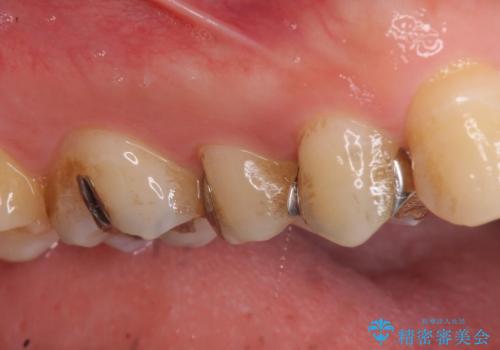

- 右上の銀歯を白くしたいといらっしゃった方の症例です。

右上4、5番目の歯はオールセラミッククラウンによる補綴、6番目の歯はセラミックインレーによる修復を行いました。

セラミックインレーについて

当院のセラミックインレーはemaxという強度と審美性に優れた材料を使用しています。

またプレス方式でインレーを製作しているため、削り出しで製作するCADCAMより優れた適合性も持ち合わせており、虫歯が再発しにくい修復物です。